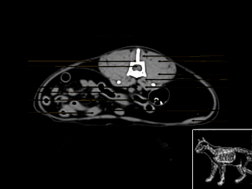

Atlas abdomen du chien SCTO

Scanner tissu osseux

>> 44 coupes

Atlas abdomen du chien SCTM

Scanner tissu mou

>> 43 coupes

Atlas abdomen chat SCTO

Plan des coupes transversales

Atlas abdomen du chat SCTM

Plan des coupes transversales